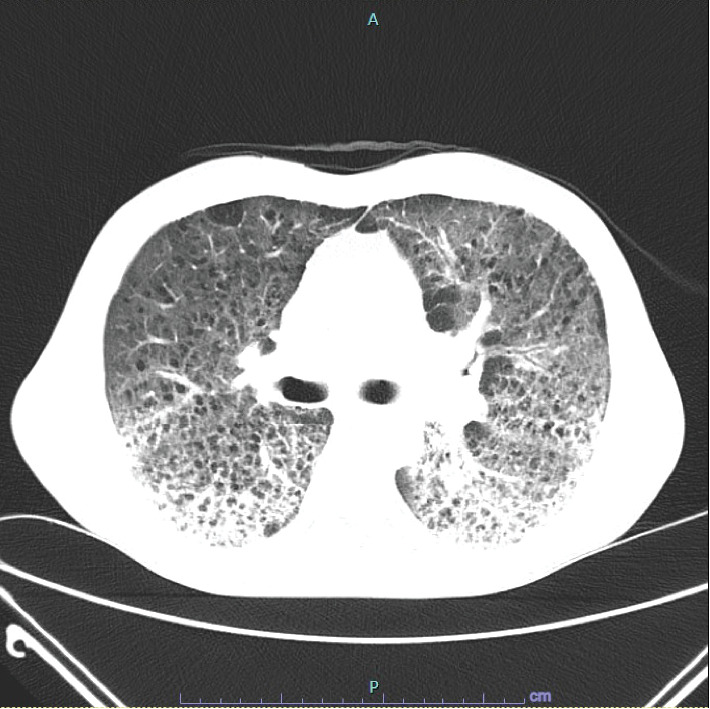

丝裂霉素C (MMC)肺炎导致急性呼吸窘迫综合征(ARDS)是一种罕见的危及生命的MMC不良反应。诊断MMC肺炎可能具有挑战性,因为更常见的病因(如细菌感染)往往是首先针对的目标,因为患者因化疗而免疫功能低下。我们报告了一例中年男性服用MMC而不同时服用长春花生物碱的病例,他发生了继发于MMC肺炎的ARDS,需要插管和重症监护。患者在服用抗生素多日后,经类固醇治疗恢复,未发现感染性病因。这个病例强调了认识到MMC是可能导致急性呼吸窘迫综合征和死亡的肺炎的潜在病因的重要性。

Mitomycin C (MMC) pneumonitis leading to acute respiratory distress syndrome (ARDS) is a rare and life-threatening adverse reaction to MMC. Diagnosing MMC pneumonitis can be challenging as more frequent etiologies such as bacterial infections are often targeted first due to patients being immunocompromised from chemotherapy. We report a case of a middle-aged male who was administered MMC without concomitant vinca alkaloid, who developed ARDS secondary to MMC pneumonitis requiring intubation and intensive care. The patient recovered with steroid treatment after being on antibiotics for many days, and no infectious etiology was ever identified. This case emphasizes the importance of recognizing MMC as a potential cause for pneumonitis which can lead to ARDS and death.